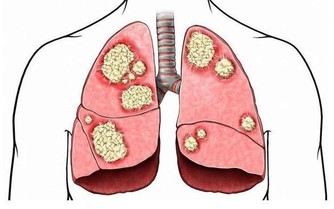

1、觀察自己的雙手,如果發現指尖比指節更粗大,可能是患有較嚴重的肺部疾病;

鼻子不靈,同時經常咳嗽,有時甚至呼吸困難,這是肺功能逐步衰退的標誌。

病人首先要注意飲食,戒菸或者控制吸菸量,也不要和經常吸菸的人在一起。

多吃新鮮瓜果和蔬菜,加強體質鍛鍊,防止肺部合併症的發生。